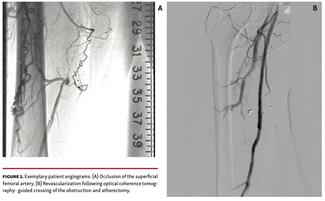

Juying Qian, MD; Hua Shen, MD; Jun Guo, MD; Zhijun Sun, MD; Yu Wang; Lian Chen, MD; Yundai Chen, MD; Qinhua Jin, MD; Yujie Zhou, MD; Jing Jing, MD; Yizhe Wu, MD; Yuyang Liu, MD

The study sought to assess the effectiveness and safety of the novel P60 Vivolight frequency-domain optical coherence tomography system (Shenzhen Vivolight Medical Device & Technology).